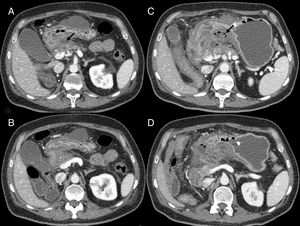

Intestinal perforation (Fig. 2): bevacizumab, sorafenib and sunitinib are known to be associated with intestinal perforation, apparently caused by their interactions with the microvasculature, causing ischaemia and thrombosis of the vessels.7,8 The risk of perforation is also greater in colon cancer and renal cell carcinoma.7,9 In computed tomography (CT), intestinal perforation may be seen as pneumoperitoneum, but also as intra-abdominal free fluid, discontinuity in the intestinal wall, thickening of the intestinal wall and abscess formation.7,9 Intestinal perforation primarily occurs during the first six months of treatment.8

Figure 2.Intestinal perforation associated with VEGF-targeted therapy. Case 1 (A): 46-year-old woman with ovarian cancer being treated with bevacizumab. Computed tomography (CT) shows pneumoperitoneum (arrow) and free fluid (star) in the context of an intestinal obstruction. This obstruction was not very serious; the intestinal wall was probably weakened due to bevacizumab. Case 2 (B–D): 71-year-old male on second-line treatment with a paclitaxel-ramucirumab regimen for metastatic recurrence of gastric adenocarcinoma. (B) CT obtained during admission due to pyrexia and abdominal pain after the 2nd cycle: new-onset ascites and thickening of the transverse, descending and sigmoid colon in relation to colitis (arrow). Corticosteroid treatment and a watch-and-wait approach adopted as the patient showed clinical improvement. (C and D) CT of abdomen and pelvis performed one week later due to clinical worsening: persistence of the colitis (arrow) observed, as well as new-onset pneumoperitoneum (star) due to intestinal perforation.